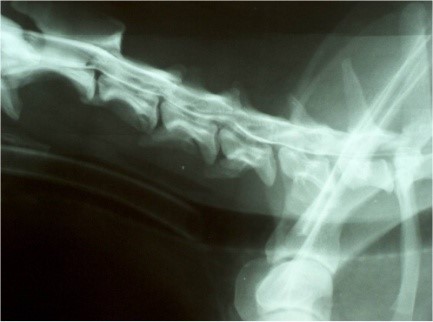

Kontraszt stop L2-3 között

Thoraco-lumbalis kontrasztstop